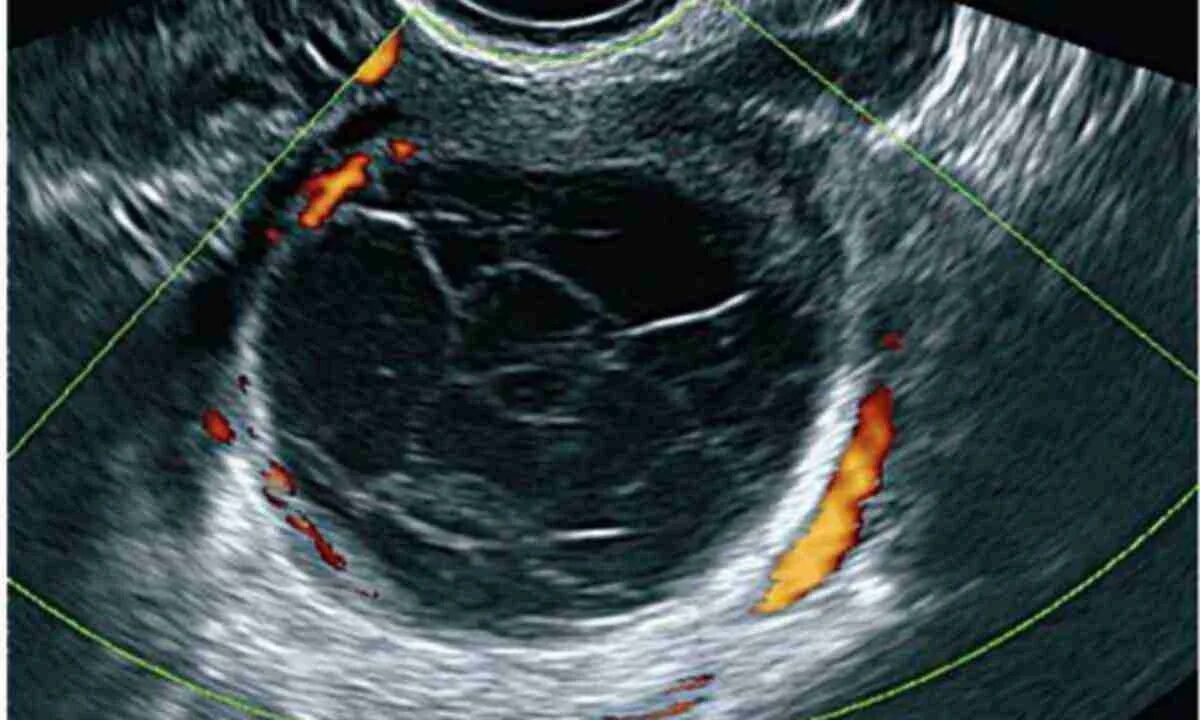

Как выглядит яичник